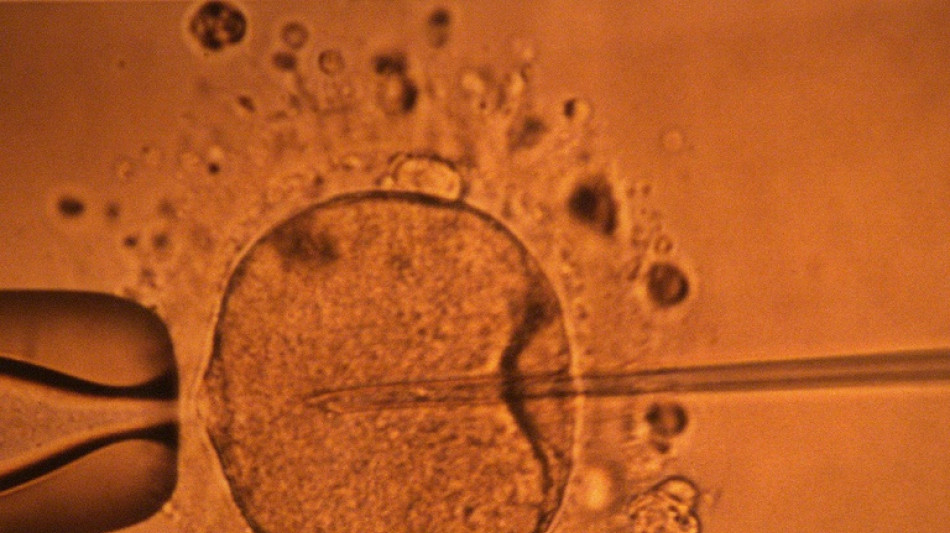

La concentración de espermatozoides, uno de los factores de la fertilidad masculina, disminuyó significativamente en todo el planeta en las últimas décadas, según un estudio publicado el martes.

"La concentración de espermatozoides disminuyó significativamente entre 1973 y 2018", resumen los autores de este trabajo publicado en la revista Human Reproduction Update y realizado mediante la compilación de unos 40 estudios previos.

La cantidad de espermatozoides es uno de los factores que afectan a la fertilidad masculina, pero no es el único.